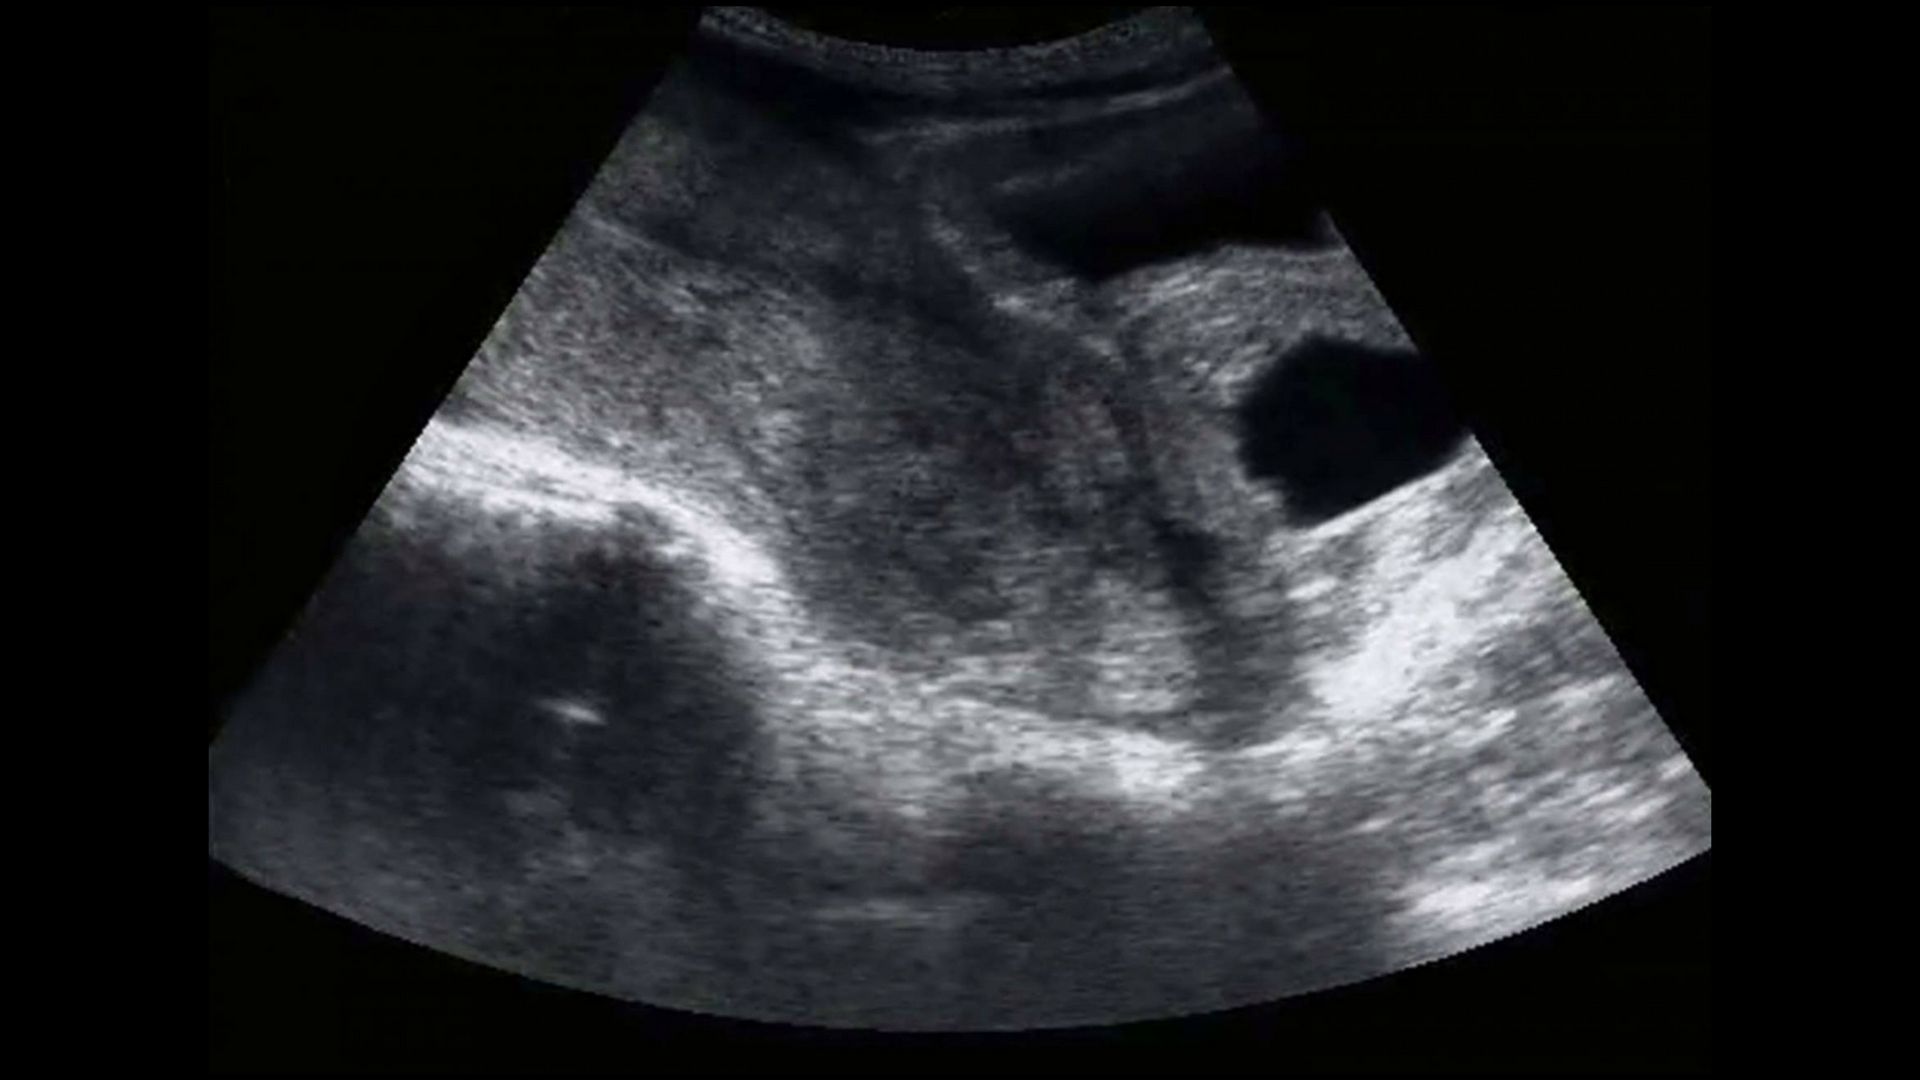

Młoda kobieta swoją historią postanowiła podzielić się na Facebooku. Publikując zdjęcie USG na początku napisała – "proszę najpierw przeczytaj, później oceń" . Swoją opowieść zaczęła od tych słów:

Ale moje zdjęcia USG były inne niż te, które widziałam na Facebooku wstawiane przez wszystkie moje koleżanki. Wiedziałam, że coś jest nie tak. Jeszcze wtedy nie wiedziałam tylko, że jestem kilka godzin po poronieniu" - pisała na Facebooku i Instagramie Emily.

Zdjęcie USG Emily, pod którym opublikowała list

Zdjęcie USG Emily, pod którym opublikowała list © Facebook

Kobieta opisuje, że w gabinecie nagle nastała wymowna cisza. W pewnym momencie lekarze przeprosił i wyszedł z sali. Mąż nieustannie zapewniał ją, że na pewno wszystko jest dobrze. Emily opowiada, że patrzać na swoje USG wiedziała, że obraz nie wyglądał tak samo, jak inne.

Dodała również, że prześledziła i oglądała wiele zdjęć w Internecie wpisując w wyszukiwarkę "zdjęcie USG 8 tygodni". Dziewczyna opisuje, że nie była w stanie powstrzymać łez. Jeszcze bardziej nie mogła patrzeć w oczy męża, które były pełne bólu. On też w głębi serca wiedział, że nie jest dobrze.